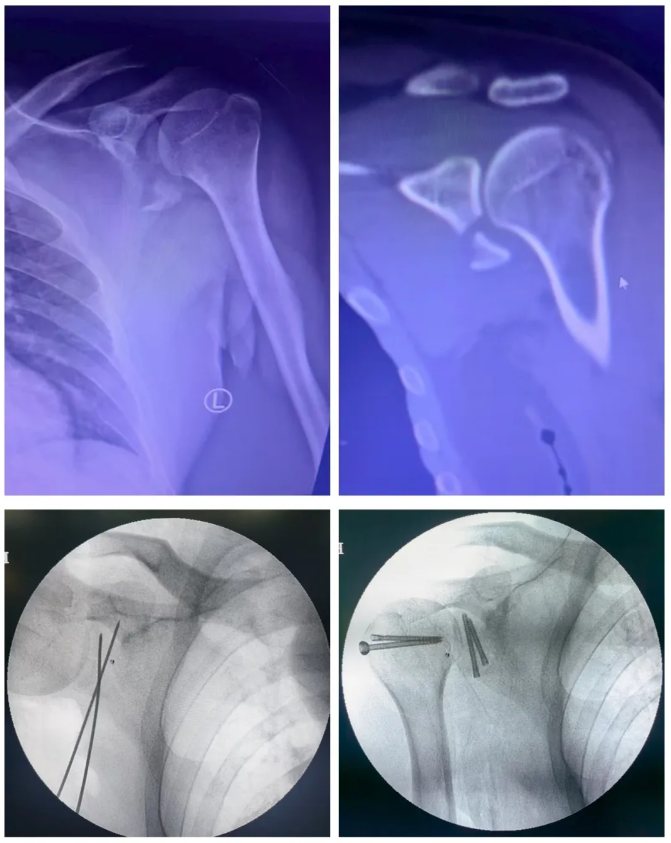

日前,白银市中心医院骨关节外科常敬忠主任团队成功完成了医院首例经腋窝入路治疗肩胛盂前下缘骨折复位内固定手术。这位34岁的男性患者因交通事故导致左肩关节盂骨折合并肱骨大结节撕脱性骨折,术后恢复良好,肩关节疼痛明显缓解、功能显著改善。

患者因交通事故导致左肩关节剧烈疼痛和活动受限。经影像学检查确诊为左肩胛盂骨折合并肱骨大结节骨折。肩胛盂骨折约占肩胛骨骨折的10%,而肩胛骨骨折仅占全身骨折的0.1%。

肩关节盂位于肩胛骨的外侧角,是肩胛骨的重要组成部分,在肩胛骨与其他邻近骨骼的连接中起着关键作用。面对这一复杂损伤,医院骨关节外科常敬忠主任团队进行了全面评估。他们认为,传统手术方式虽然技术成熟,但存在切口大、出血多、术后肩关节功能恢复欠佳等缺点。而腋窝入路是一种创新手术方法,被誉为“精准治疗与美学康复”的深度融合。与传统手术相比,腋窝入路切口隐蔽、损伤范围小,因其经过肌肉、神经及血管的生理性间隙进入,术后恢复较快。

腋窝入路技术对医生的操作能力有很高要求。手术部位血管、神经纵横交错,操作区域解剖结构复杂。医生需要识别背阔肌、肩胛下肌,分离筋膜,并识别和保护重要的神经血管结构,如腋神经、胸背神经和旋后动脉、肩胛血管和肩胛下血管,只有在暴露清晰完全后,才能可靠地复位和固定关节盂骨折。整个过程要求术者对肩关节三维解剖有“透视级”的掌握。采用腋窝入路手术后,患者康复进程显著加快。关节功能恢复快,疤痕几乎隐形,满足了患者夏季自由穿衣的社交需求和疤痕尴尬。住院时间较传统手术方式减少3至4天,费用相应降低。